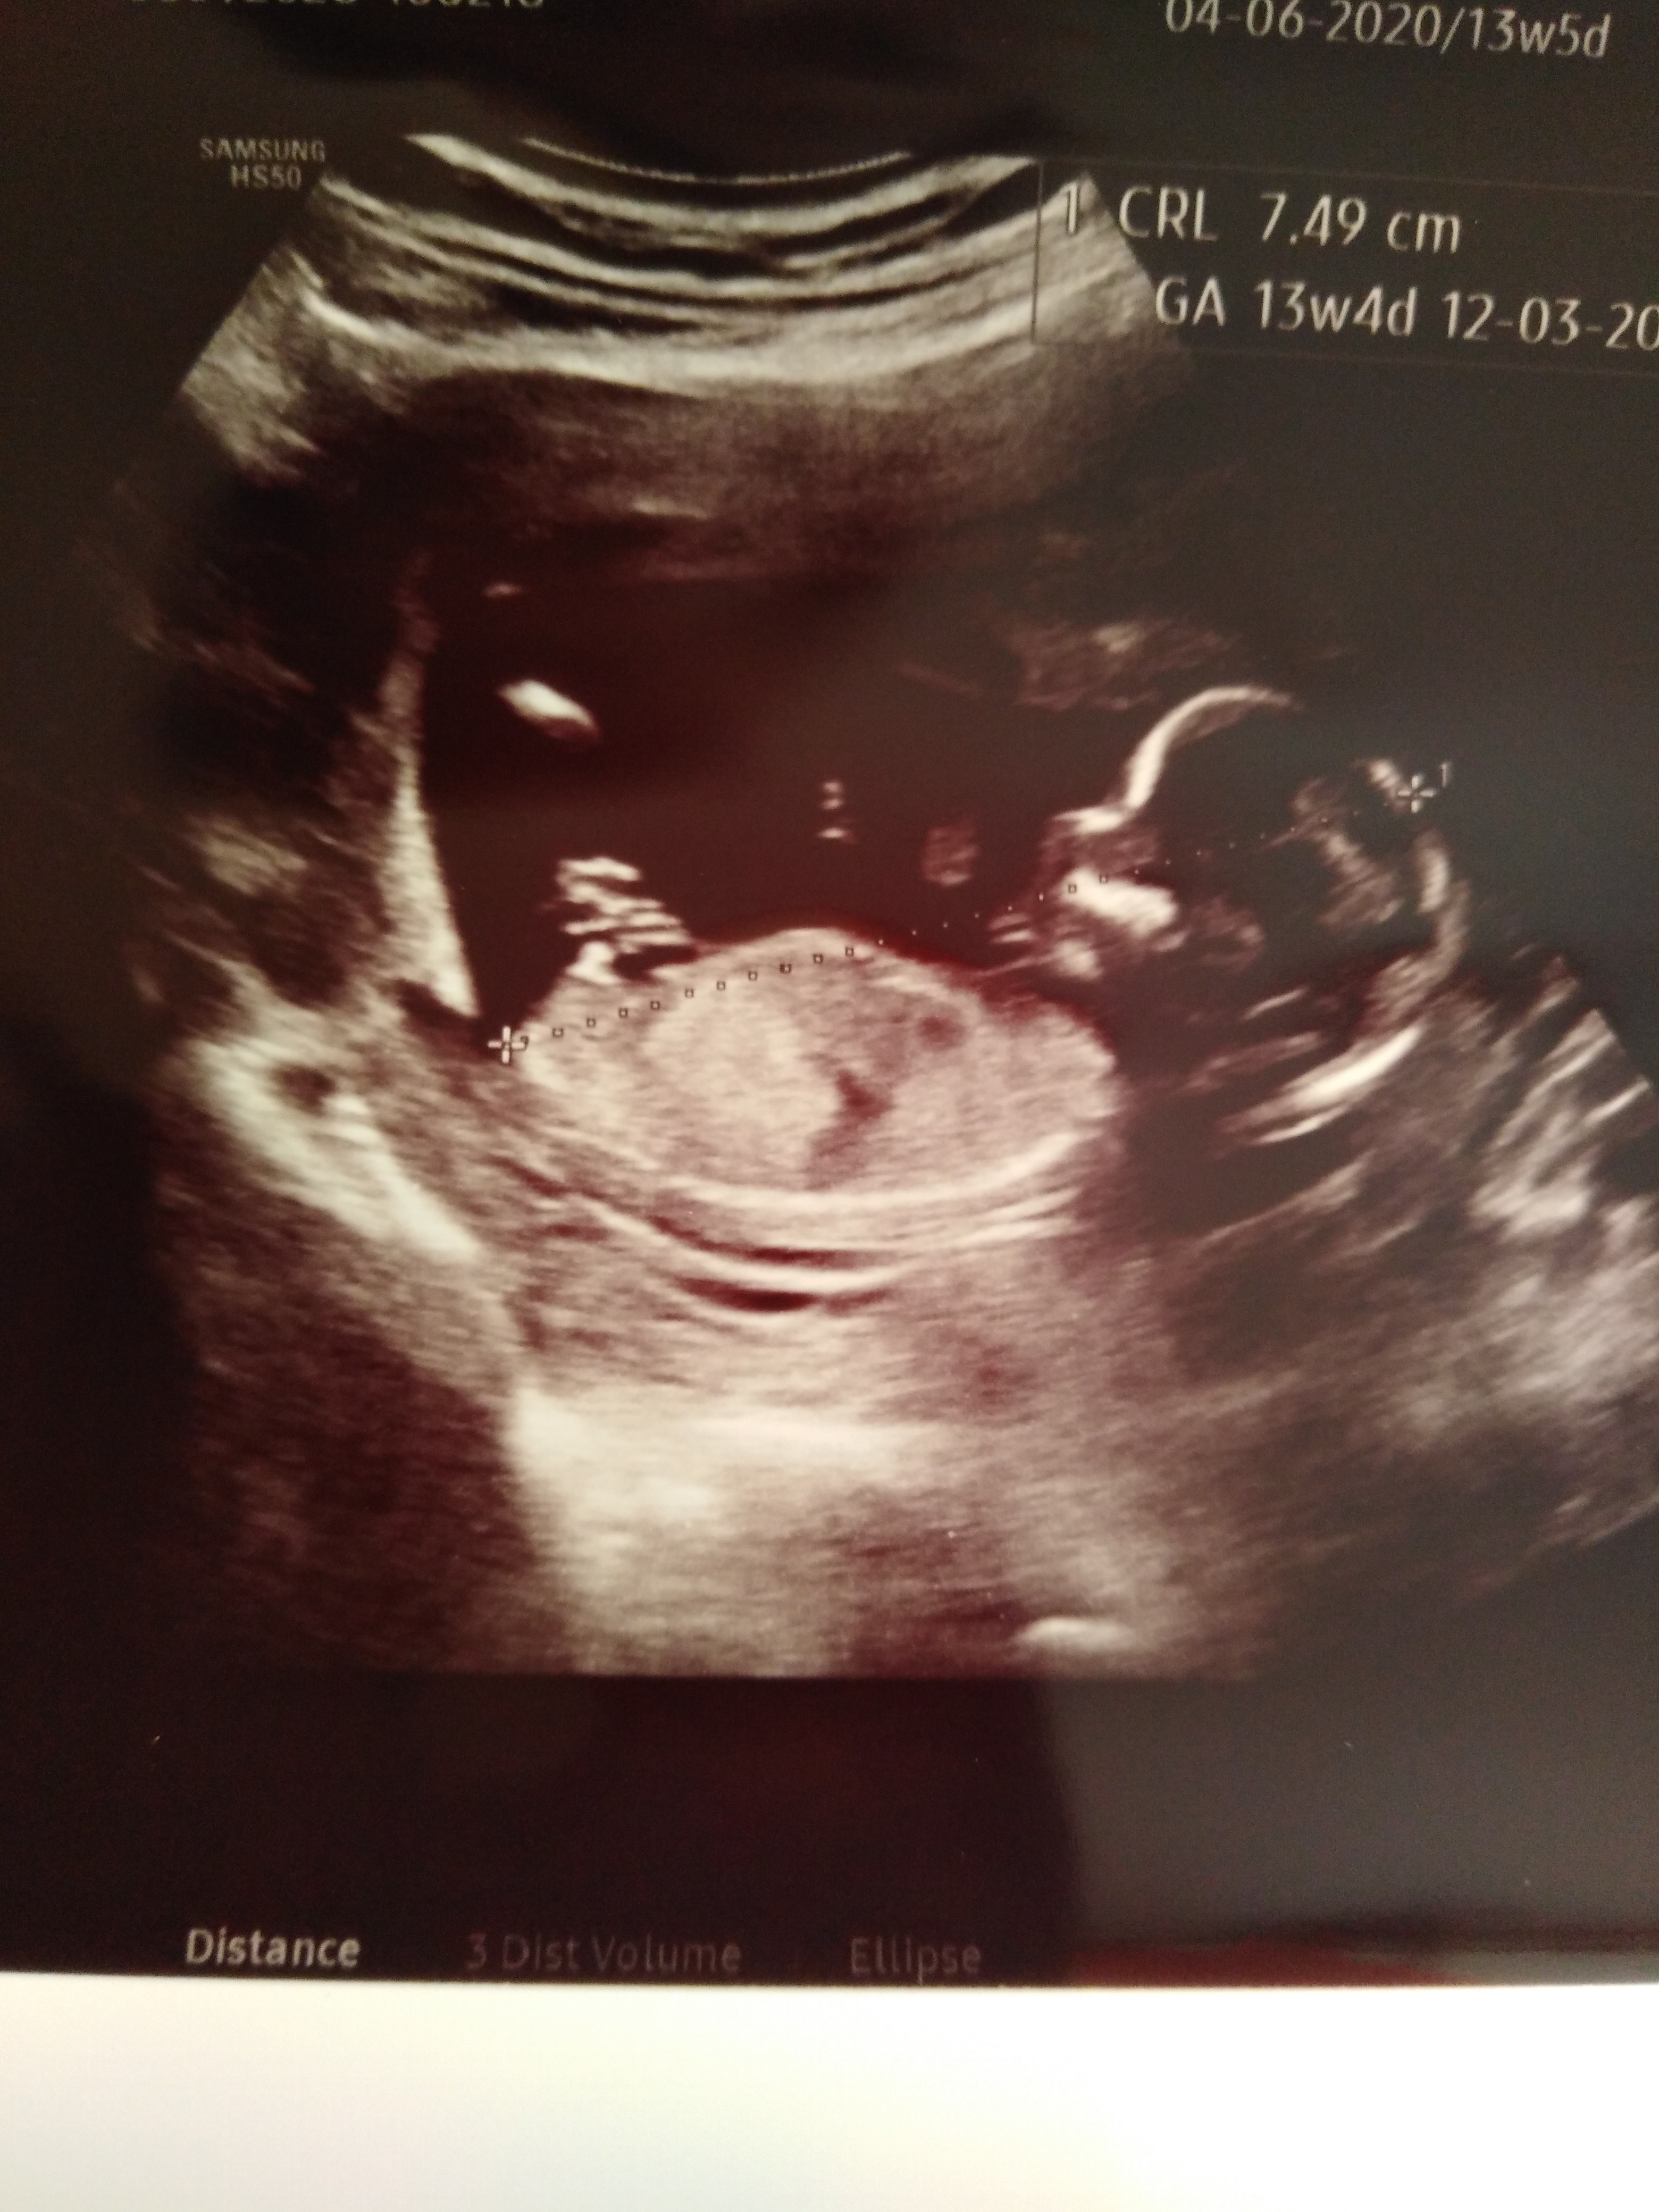

I po prenatalnych wszystko super😁 wg om 13t5d wg usg 14t1d crl 7.49cm dzieciak nie bardzo chciał współpracować bo kręcił się niemiłosiernie ale dla mnie to boski widok był 🤩